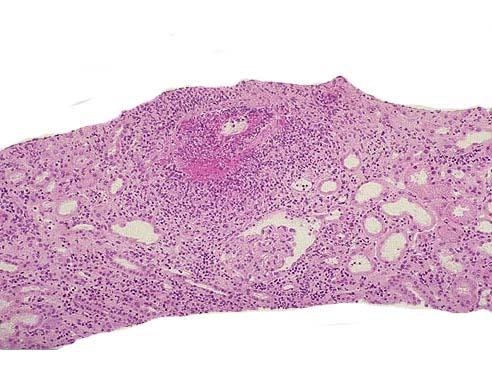

问题 韦格氏肉芽肿患者病变部位镜下可出现如图所示改变,下列关于该病说法错误的是 ( )

选项 A.30~50岁多见,男性略多 B.在动脉壁、动脉周围或血管外部区域出现肉芽肿炎症 C.多数患者出现不同程度的肾小球肾炎 D.肾脏病变常为局灶坏死性肾小球肾炎伴新月体形成 E.严重者可引起急性肾功能衰竭

答案 E